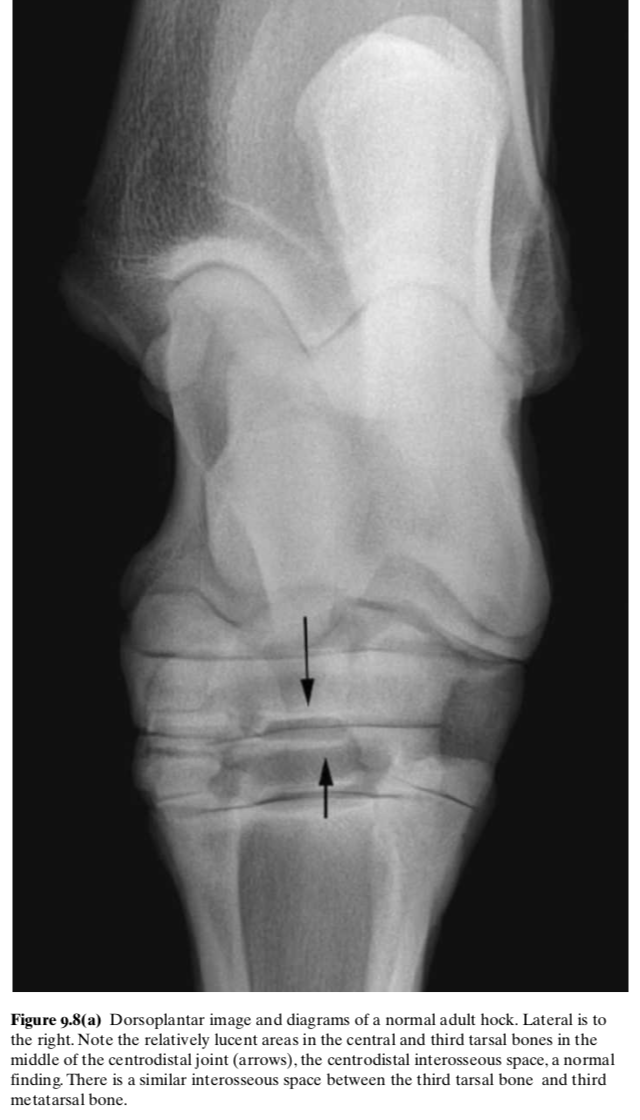

Lucent region in the DIT on DP rad

The centrodistal interosseous space, a normal finding